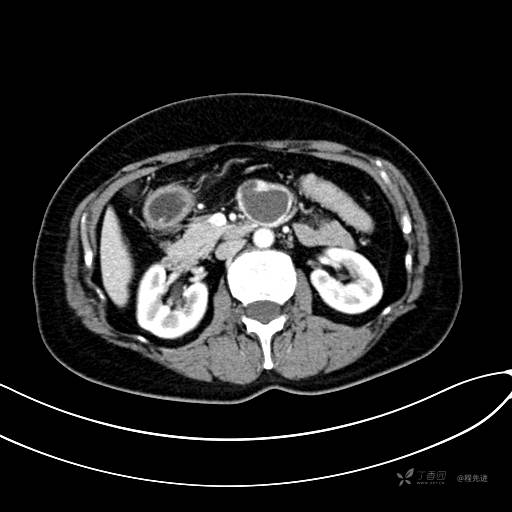

CT增强门脉期